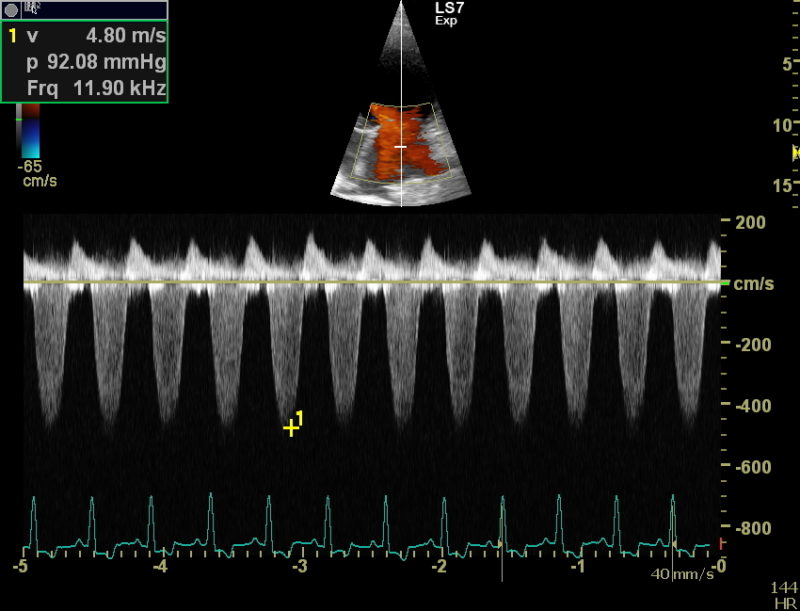

Weitergehend haben wir dann eine Herzultraschalluntersuchung durchgeführt um weitere Informationen über die zugrundeliegende Erkrankung zu bekommen. Auch in der Echokardiografie stellte sich das Herz deutlich zu groß da. Die linke Hauptkammer und der linke Vorhof sind massiv volumenüberladen, also mit zu viel Blut gefüllt. Durch die starke Blutfülle im Herzen hat sich auch der Klappenapparat der Mitralklappe aufgedehnt, sodass dieses Rückschlagsventil zwischen der linken Kammer und dem linken Vorhof nicht mehr richtig abdichtet. Resultat ist eine Mitralklappeninsuffizienz, die bei jedem Herzschlag etwas Blut in den linken Vorhof zurückfließen lässt. Der linke Vorhof wird, wie hier bei Faust sehr groß und das Blut staut in den Lungenkreislauf zurück, es entsteht ein Lungenödem. Vereinfacht gesagt Faust hat „Wasser auf der Lunge“, eine weitere wichtige Ursache für Husten bei unseren herzkranken Hunden. Die Herzmuskulatur bei Faust ist eher dünn und die Pumpkraft (Kontraktilität) der Herzmuskulatur ist sehr schwach.

Bei der Kontrolluntersuchung am 5. März mussten wir leider eine weitere Verschlechterung der gemessenen Werte feststellen. Faust hatte einige Tage zuvor wieder zu husten begonnen, das Blutvolumen im linken Herzen hatte noch einmal zugenommen, lediglich die Pumpkraft des Herzens war etwas besser als bei der Erstuntersuchung. Wir haben die Dosierungen der Herzmedikamente noch einmal angepasst und hoffen, dass es unserem Patienten nun noch lange gut geht.